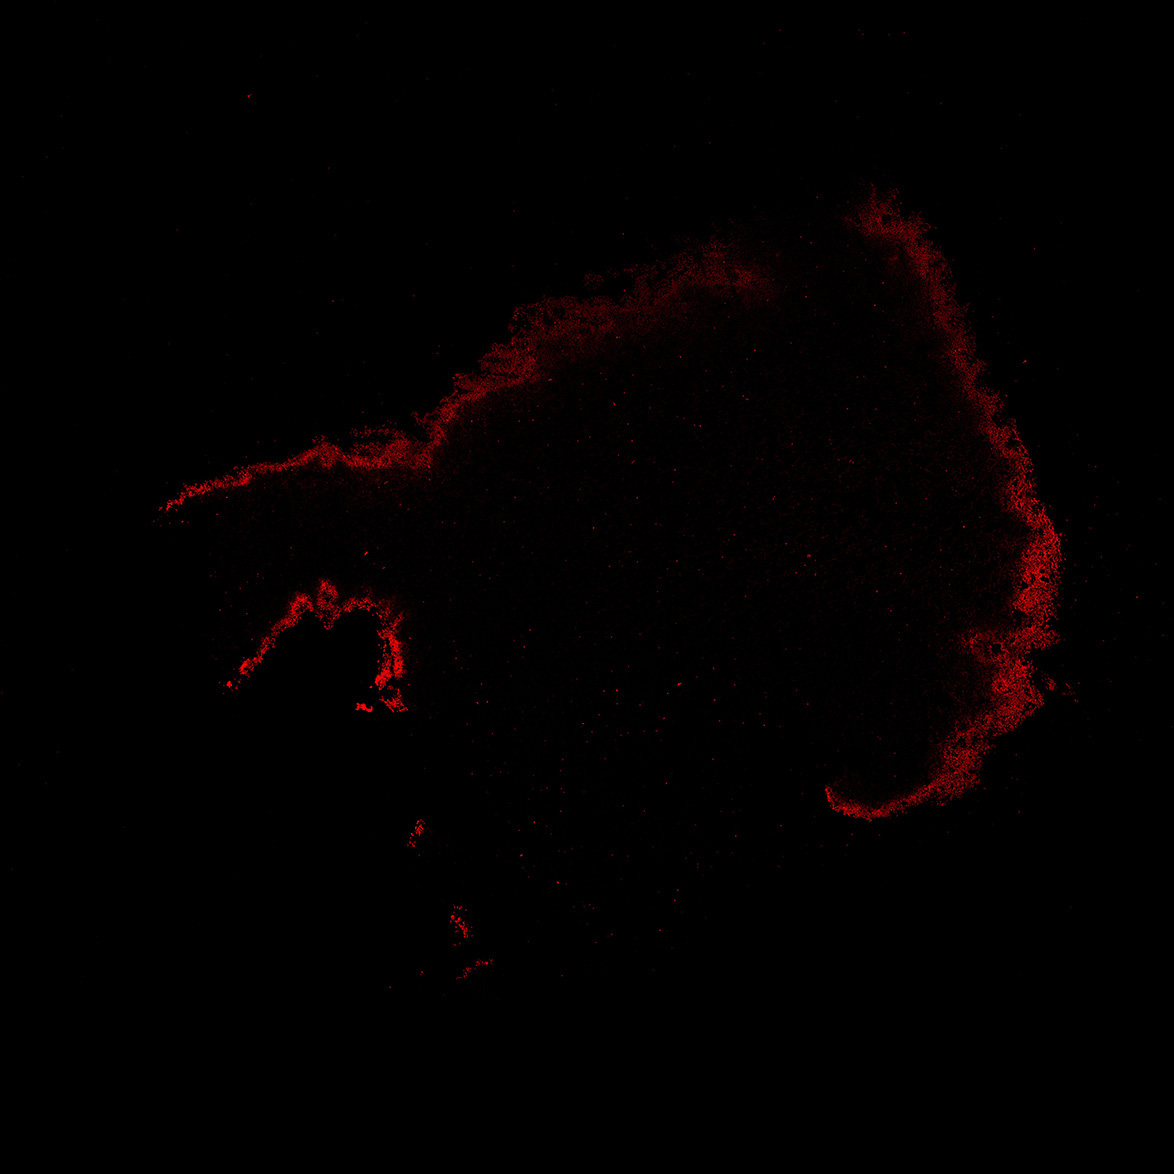

An anatomical analysis of the developing human midbrain from 6 post-conceptional weeks (PCW) to 22 PCW reveals increased tissue complexity, characterized by the emergence of dopaminergic nuclei, as highlighted by immunofluorescence analysis for tyrosine hydroxylase (TH).

15PCW

DAPI

15PCW human midbrain

MAP2

TH

Merged